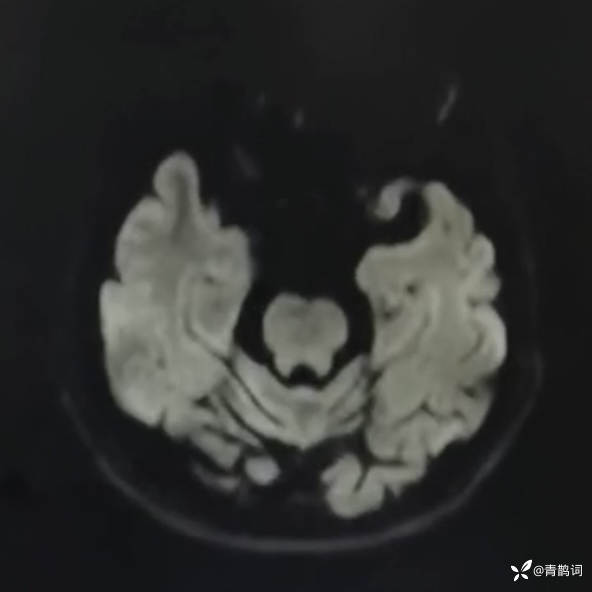

乐痴于医等 2人推荐简要病史:42岁男性,记忆力下降及听力下降一年余。既往体健,否认前驱感染病史。否认家族史。三个月前就诊于当地医院,自述腰穿脑脊液乳酸增高。现就诊于我院,查体记忆力下降,计算力下降,定时定向差,吟诗样语言。完善磁共振如下:

DWI:

2.患者小脑萎缩严重,和大脑半球的病灶之间有无关系?能否用一元论解释?